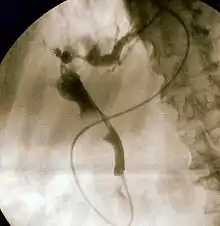

- To undergo ERCP for diagnosing diseases of biliary tree or their management